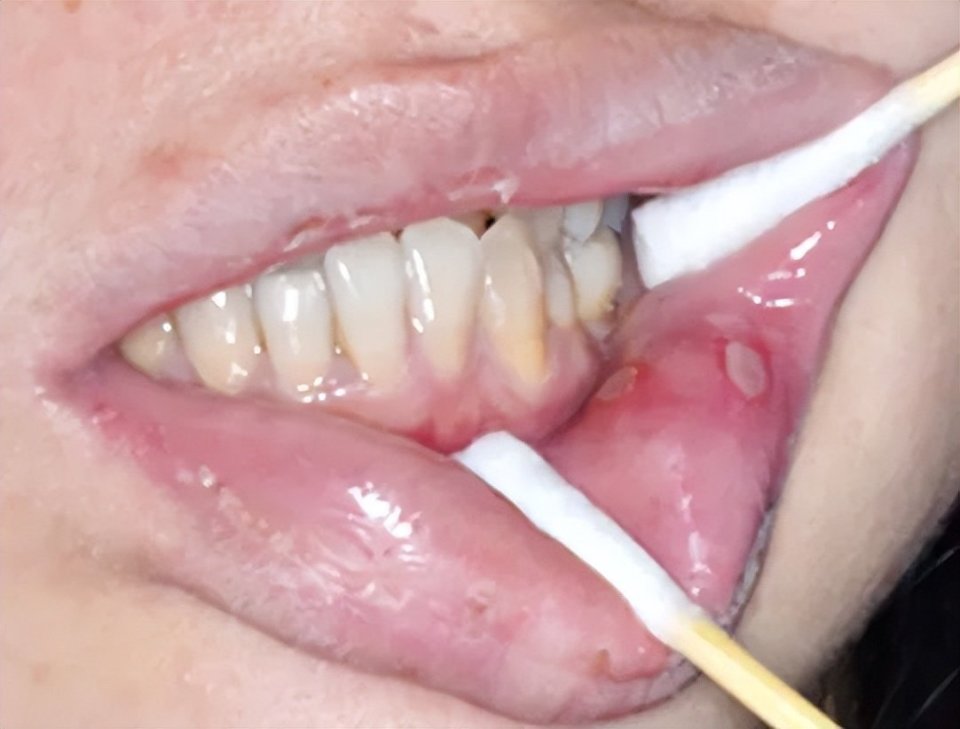

溃疡形成及苔藓样损害(图片源自陶人川教授团队)